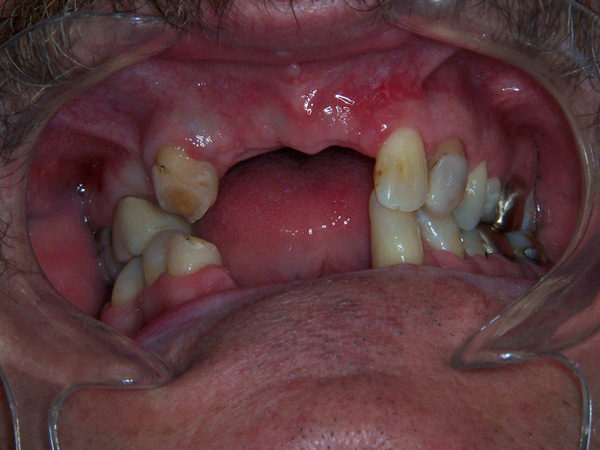

Case Study 3

Problem: This gentleman had an accident with a four-wheeler which gave him multiple jaw fractures and broken teeth. As a result of his accident, it left him with no teeth in the upper and lower front.

Plan: Our plan… the fractures were fixed and three implants were placed on the upper arch and two implants on the lower arch bridging the missing teeth. We also fixed a few broken teeth with root canals and crowns.

Don’t let accidents ruin your smile.